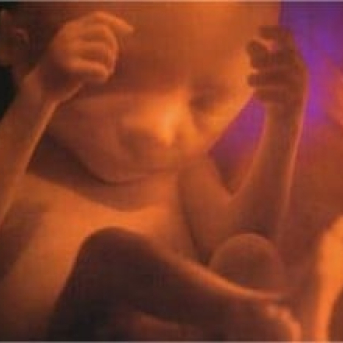

Como está o bebê com 6 meses de gravidez?

O bebê com 6 meses já está exatamente do jeitinho que estará no dia do nascimento, mas ainda com baixo peso. Ele já tem tudo formado, inclusive cílios e sobrancelhas, que proporcionam sua fisionomia completa. Agora o seu foco é o ganho de peso que irá aumentar em torno de 500 gramas por semana a partir de agora.